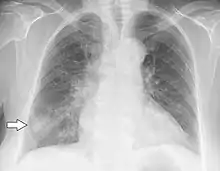

Chest X-ray of a patient who first had influenza and then developed Haemophilus influenzae pneumonia, presumably opportunistic